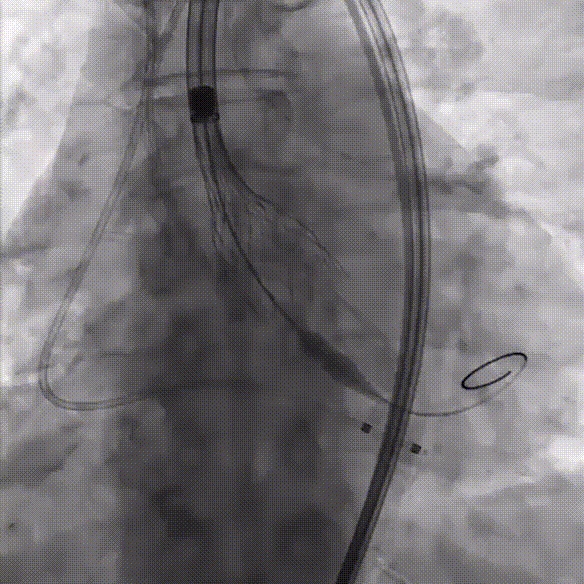

2、通过Evolut PRO inline sheath内联鞘,送入26mm Evolut PRO瓣膜,顺利完成过弓、跨瓣;

过弓

跨瓣

3、造影确定瓣膜到位,180bpm快速起搏下精准释放瓣膜;初次释放瓣膜位置稍高,半回收轻微向前推送后继续释放瓣膜,释放至80%时根部造影结果显示无瓣周漏,左右冠脉均有显影,冠脉血流未受影响,继续完成释放;

部分释放

冠脉造影

完全释放

术后根部造影